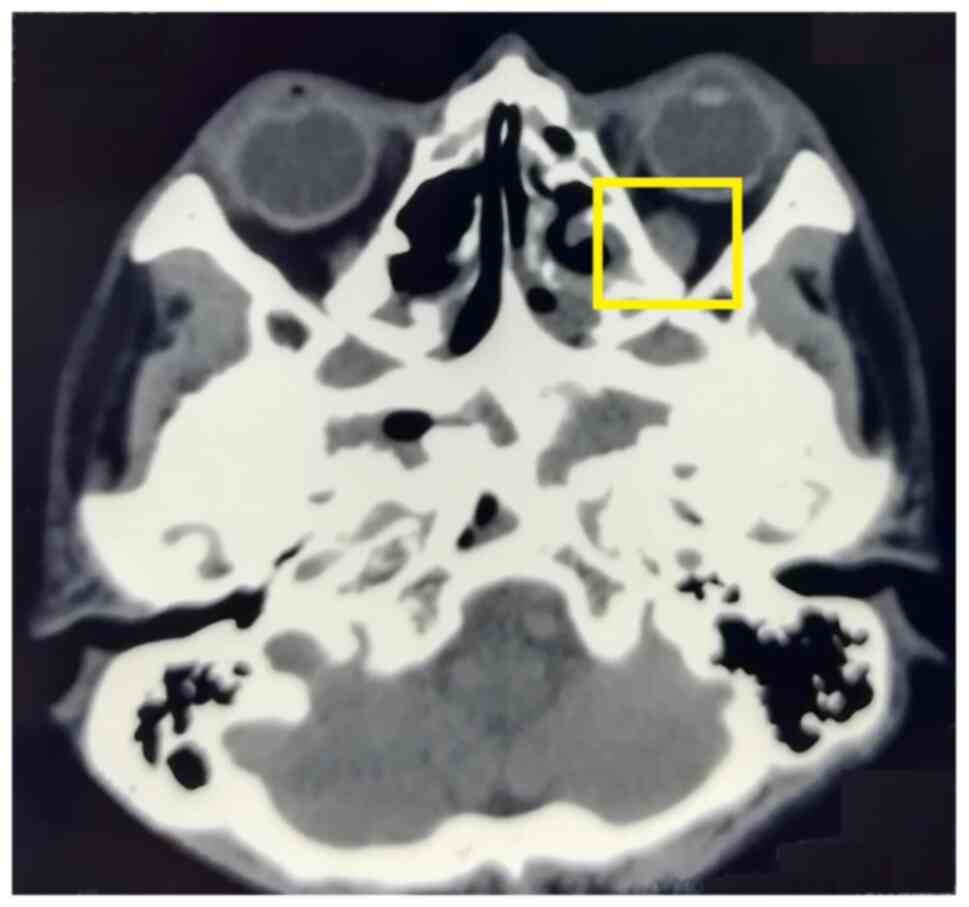

The lymph nodes of the bilateral neck, bilateral supraclavicular fossa and submandibular gland became smaller on the ultrasound scan. The lymph node grade at the first two sites changed to grade 2, excluding malignancy. Orbital CT revealed that the enlarged left inferior rectus muscle became slightly narrowed (Fig. 6). The visual acuity of both eyes exhibited marked improvements and the vision of both eyes increased to 1.0.

Figure 6

Slight narrowing of the enlarged left inferior rectus muscle after three months of treatment was observed on orbital CT (highlighted area).